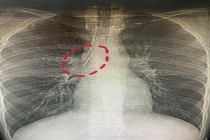

男子体检发现胸腔藏了一根缝衣针 十余年“与针共存”奇迹

17岁的小陆在一次参军体检中意外发现了一个隐藏多年的秘密:一根长达5厘米的锈迹斑斑的缝衣针藏在他的胸腔里。这根针紧贴大血管、刺入肺组织,多年来竟毫无痛感,未引发...